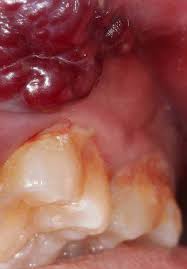

What Does Mouth Cancer Look Like On The Tongue : Oral Cancer Images The Oral Cancer Foundation - Mouth cancer typically affects your cheeks, lips, tongue, or throat.. Tongue cancer is a type of mouth cancer, or oral cancer, that usually develops in the squamous cells on the surface of the tongue. In the early stages of tongue cancer, especially with cancer at the base of the tongue, you might not notice any symptoms. If tongue cancer is suspected, a physician can perform biopsies and various scans to confirm a diagnosis 2. It usually shows up as flat, white patches on any of those areas. On the other hand, cancer affecting gingiva, gums, the floor of the mouth and soft palate have a poor outlook.

What Are The Causes Of Mouth Cancer Cancer Healer Center from www.cancerhealercenter.com A white or red patch inside your mouth or on your lips may be a potential sign of squamous cell carcinoma. Health scotland and glasgow dental hospital. The main risk factors are smoking, drinking a lot of alcohol and infection with the hpv virus. It doesn't simply thrive on top of the material it spends the tissue. Oral cancer starts in the mouth. Just to remind you about what some oral cancers look like. Tongue cancer is a type of head and neck cancer. A canker sore looks like an ulcer, usually with a depression in the center.

Individuals who smoke or consume large amounts of alcohol are at an increased risk and need to be screened regularly. Mouth cancer usually presents with distinctive symptoms and features, such as red or white patches in the mouth, changes in oral tissue, or difficulty chewing or swallowing. Seeing a red or white patch on you gums, lining of mouth, tonsil or tongue is a sign of squamous cell carcinoma. Oral cancer can affect the mouth including the gums, lips, tongue, mouth's roof, and floor and the inner cheeks. One of the most common questions asked by new members in canker sore forums, is what does a canker sore look like? which is understandable as there are many weird things that can happen in your mouth. It is highly advised to have a dental checkup once a year as your dentist can locate any abnormal growth or patch that can ultimately transform into malignant cancer. A shallow ulcer on the lower lip. Although ulcers and lesions in the mouth are often canker sores — which are relatively harmless — some can be oral cancer. It usually shows up as flat, white patches on any of those areas. Mouth cancer typically affects your cheeks, lips, tongue, or throat. The most common early symptom of tongue cancer is a sore on your tongue. The patches having a grayish or white coloring to them present on your lips or inside your mouth are known as keratosis or leukoplakia. The impact of mouth cancer..

Oral Cancer Dr Kanishk Mehta Udaipur from productimages.withfloats.com Floor of the mouth cancer is cancer that begins on the tissue underneath your tongue. Tongue cancer is a type of mouth cancer, or oral cancer, that usually develops in the squamous cells on the surface of the tongue. Mixed red and white patches and bright red patches are also signs of trouble. It may be numb or firm to feel and doesn't fade away over time. Tongue cancer is highly curable if caught in the early stages 2. The hardest part of recovery: A red patch under the tongue. Smokers are five times more likely than nonsmokers to develop oral tongue cancer.

When we talk about tongue cancer, we usually mean cancers of the oral tongue. Mixed red and white patches and bright red patches are also signs of trouble. The american cancer society estimates that 28,000 people in the united states develop oral or throat cancer each year and 7,000 die from it. Mouth cancer usually presents with distinctive symptoms and features, such as red or white patches in the mouth, changes in oral tissue, or difficulty chewing or swallowing. In the early stages, mouth cancer rarely causes any pain. Canker sores can be found anywhere in the mouth from the cheek, inner lip, on and under the tongue, and even in the throat. The tongue is actually a large muscle in the mouth that has two parts, the oral tongue is the part that is visible inside the mouth that is used to speak and eat, while the base of the tongue is farther back, and is part of the throat. It doesn't simply thrive on top of the material it spends the tissue. These photos give you an idea of what possible mouth cancers can look like, but remember that they might appear differently to this. In most cases, there is no identifiable cause for cancer of the mouth in dogs. A patch on your tongue, gums, tonsils, or the lining of your mouth can signal trouble. Tongue cancer is a terribly invasive cancer. Oral cancer starts in the mouth.

Do to the location of my tongue cancer which is at the base of the tongue (can not be seen without bent mirrors or a remit) radiation is no other course of action. They may look like a patch or a lump or look like an ulcer. Floor of the mouth cancer is cancer that begins on the tissue underneath your tongue. When possible, use one finger inside your mouth and one finger on the outside, corresponding to the same place and feel for unusual bumps, swelling or tenderness. Seeing a red or white patch on you gums, lining of mouth, tonsil or tongue is a sign of squamous cell carcinoma.

A white or red patch inside your mouth or on your lips may be a potential sign of squamous cell carcinoma. Some symptoms of mouth cancer are noticeable, that makes it possible to detect mouth cancer in its early stages. Women and people of 45 years of age and above are more vulnerable to. Oral cancer can pose a serious health risk.consequently, many patients become concerned when they develop unusual spots or sores in the mouth. Removable devices that look like dental retainers can fill in for lost tissue or. Individuals who smoke or consume large amounts of alcohol are at an increased risk and need to be screened regularly. Mouth cancer of the lips and tongue have a better prognosis. These patches are made up of cells that can lead to cancer. It can begin in the lips, tongue, gums,. It's important to be aware of the symptoms of mouth cancer so you can contact your gp or dentist if you notice anything abnormal. Floor of the mouth cancer most often begins in the thin, flat cells that line the inside of your mouth (squamous cells). Tongue cancer is a type of mouth cancer, or oral cancer, that usually develops in the squamous cells on the surface of the tongue. They may look like a patch or a lump or look like an ulcer.